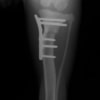

術後正面像

半年にわたる左後肢の跛行が認められるとのことで来院されました。触診にて左膝関節の疼痛、内側部の腫脹、膝蓋骨の内方脱臼を認めました。レントゲン検査にてfat pad signを伴う関節炎が認められたことから、前十字靭帯断裂と膝蓋骨内方脱臼( GradeⅢ)の併発と診断し、手術を行いました。術中の関節鏡検査にて前十字靭帯の完全断裂を確認、関節液検査にて感染を除外した後、TPLOと、滑車溝形成を始めとした膝蓋骨脱臼整復術を実施いたしました。

術前正面像

術前に25°であったTPAは、TPLO実施により7°に矯正されました。症例の歩行状態は良好です。